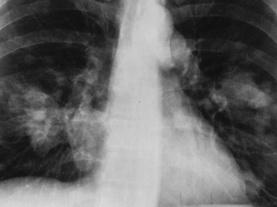

When the U.S. trade embargo left Cuba isolated from medical resources, Cuban scientists were forced to get creative. Now they’ve developed lung cancer vaccines that show so much promise, some Americans are defying the embargo and traveling to Cuba for treatment. In an unprecedented move, Cuban researchers are working with U.S. partners to make the medicines more widely available.